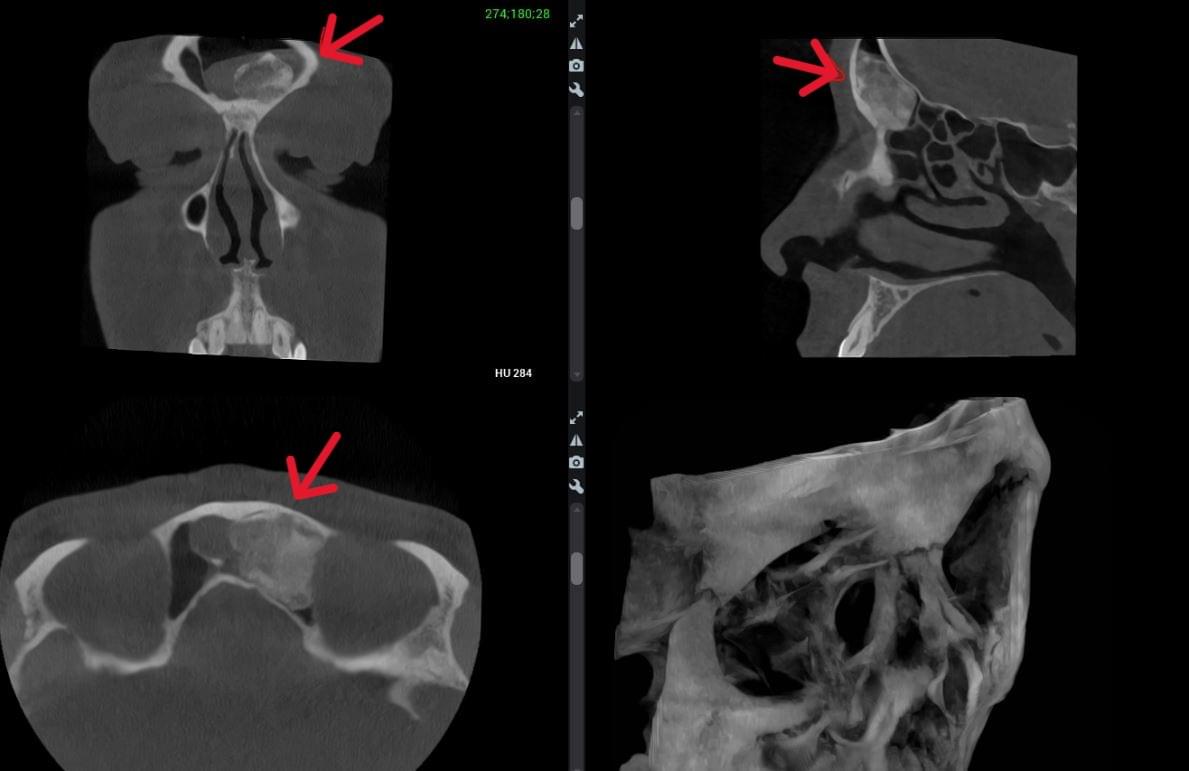

Діагностика гайморових пазух за допомогою КТ

У сучасній медицині КТ придаткових пазух носа (або КТ синусів) — це «золотий стандарт»

діагностики для ЛОР-лікарів та щелепно-лицевих хірургів. Звичайний рентген часто не

показує повну картину, а МРТ не завжди доступний і дорожчий. Комп’ютерна томографія дає

детальну 3D-модель усіх пазух (гайморових, лобних, клиновидних та решітчастого

лабіринту) за 10 секунд і з мінімальною дозою опромінення.

КПКТ (конусно-променева комп’ютерна томографія) — це 3D-знімок високої роздільної здатності. На відміну від звичайного рентгену, КТ показує:

У MyRayLab використовують сучасний апарат Planmeca 3D — доза опромінення всього 12 мкЗв (в 10–20 разів нижче, ніж у звичайних КТ), сканування 10 секунд, HD-якість.